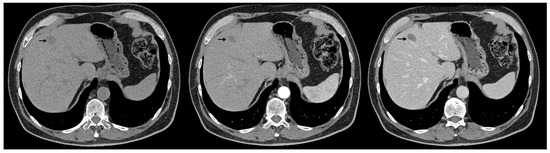

We report the case of a 67-year-old man, presented with intermittent tiredness for about three months, without associated weight loss, fever, or jaundice. The symptom was mild and episodic, occurring several times per week, and not linked to exertion or other systemic complaints. He denied abdominal pain, gastrointestinal bleeding, changes in bowel habits, cough, or flushing. From past medical history we mention chronic hepatitis C virus infection, diagnosed eight years earlier (with liver stiffness 12 kPa on transient elastography). He achieved sustained virologic response (SVR) after treatment with direct-acting antivirals (Sofosbuvir–Ledipasvir). His history also included gastric resection with gastroduodenal anastomosis for peptic ulcer disease 23 years ago, and endoscopic resection of a sessile polyp in the descending colon four years ago, confirmed as a low-grade adenomatous polyp. At the time of presentation, the patient was alert and hemodynamically stable, with vital signs within normal ranges. Physical examination revealed no jaundice, no hepatosplenomegaly, no ascites, or palpable abdominal mass, and cardiopulmonary and neurologic examinations showed no abnormalities. Laboratory investigations were within normal limits, including normal hepatic and renal function. Tumor marker levels—alpha-fetoprotein (AFP), carbohydrate antigen 19-9 (CA 19-9), and carcinoembryonic antigen (CEA)—were also within normal ranges. Abdominal ultrasound revealed three hyperechoic hepatic nodules: the largest, measuring 30 mm, in segment IVa (Figure 1a), with additional lesions in segment III (left lobe) and segment VIII (right lobe). Contrast-enhanced ultrasonography (CEUS) was performed using sulfur hexafluoride microbubbles (SonoVue®), administered as an intravenous bolus of 2.4 mL followed by a 5 mL saline flush. Arterial-phase enhancement of the hepatic nodules was observed at 10 s, with very early washout occurring at 29 s post-injection. This pattern is suggestive of malignant formations, most likely liver metastases (Figure 1b).

Figure 1.

(a) Abdominal ultrasound B-mode image capturing two hyperechoic nodules in left liver lobe (segment IVa and III) with heterogeneous, irregular contours (white arrows). (b) Abdominal ultrasound in CEUS mode at the end of the arterial phase demonstrates earlier contrast washout of both nodules compared to the rest of the liver parenchyma (white arrows).

Diagnosis relies on a multimodal approach, integrating serological test, morphological imaging, functional imaging with histopathological evaluation, and immunohistochemical profiling. Available serological tests for NENs include chromogranin A (CgA), serotonin, 5-hydroxyindoleacetic acid (5-HIAA), gastrin, insulin, proinsulin, C-peptide, glucagon, vasoactive intestinal peptide (VIP), pancreatic polypeptide (PP), calcitonin, adrenocorticotropic hormone (ACTH), somatostatin, and neuron-specific enolase (NSE). [18] Conventional ultrasound often shows strong echoic nodules but lacks specificity. CEUS is more valuable, often revealing a characteristic “fast forward and fast out” arterial hyperenhancement pattern [42]. Hepatic metastases from NENs typically present as hypervascular, ring-enhancing lesions during the arterial phase [17]. However, atypical presentations, such as pseudocystic metastases due to necrosis or hemorrhage, can mimic simple cysts, complicating diagnosis [16]. CT and magnetic resonance imaging (MRI) are standard imaging modalities for the detection and characterization of both primary neuroendocrine tumors and associated liver metastases. In our case, CT scan not only confirmed the presence of hepatic lesions but also identified an additional tumor site in the mediastinum. Functional evaluations are used to detect somatostatin receptor expression on tumor surfaces. Common techniques include 68Ga-DOTATATE PET, 64Cu-DOTATATE PET, 68Ga-OTATOC PET, and PET-CT with fluorodeoxyglucose for non-functional lesions [9,18]. These imaging methods are invaluable for staging, identifying the primary tumor, and guiding treatment decisions [43]. A limitation of this case report is the absence of functional nuclear medicine imaging, such as 68-Gallium-DOTATATE PET/CT and 18F-FDG-PET/CT. While these examinations are integral to the staging and characterization of many neuroendocrine neoplasms, the decision to forego them was made deliberately by the multidisciplinary team.